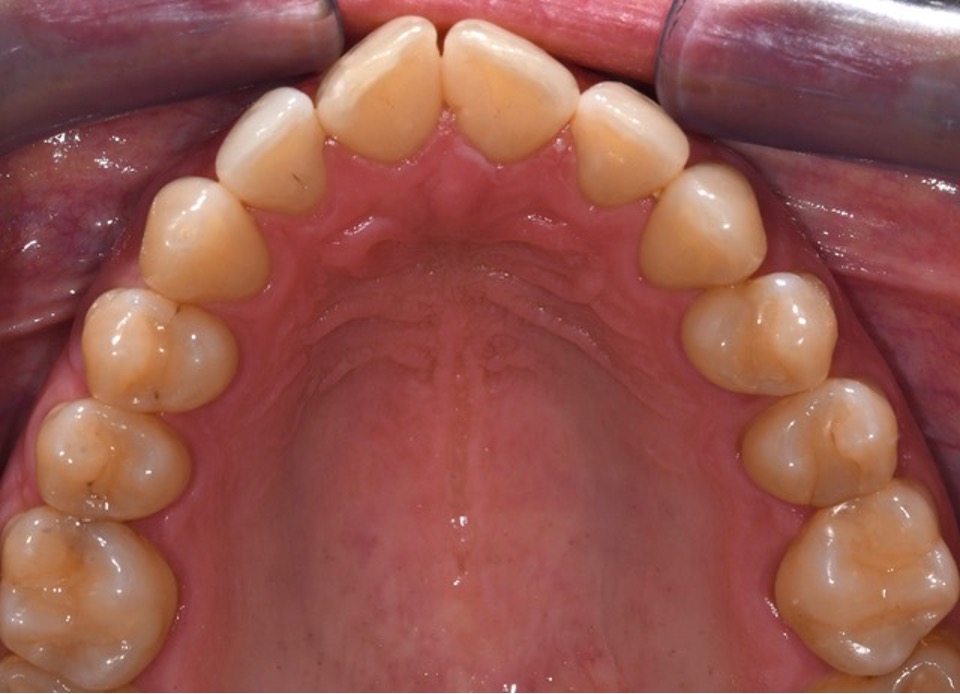

Per una visualizzazione immediata delle caratteristiche morfologiche dell’erosione dentale, ecco due esempi clinici che illustrano le differenti fasi del processo erosivo e le relative implicazioni diagnostiche.

Caso B

Erosione BEWE rischio basso (3-8)

Bulimia nervosa per 3 anni, ad oggi risolta.